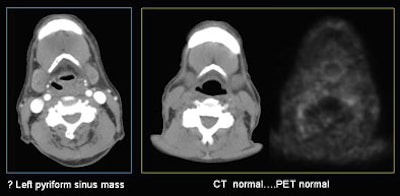

| In a patient with a history of superglottal squamous cell carcinoma, CT images acquired with a modified Valsalva breath-hold maneuver (left) closed the airway, leaving the radiologists unable to rule out a pyriform sinus mass. At right, CT acquired with the "eee" phonation showed there was no tumor. Had the "eee" technique been used initially, the PET exam (far right) would have been unnecessary. All images courtesy of Dr. Megan Strother. |

For example, in a patient with a history of squamous cell carcinoma, using the "eee" technique during the scan would have rendered PET unnecessary to rule out a pyriform sinus mass. The patient whose CT images were acquired with a modified Valsalva technique showed suspiciously asymmetric soft tissue in the region, Strother said. The group ordered PET, and eventually acquired the images again with MDCT using the "eee" technique and a breath-hold, which depicted the anatomy clearly.

"Several thousand dollars later you've got a normal PET and everybody breathes better," Strother said. "The point is we would have hoped to bypass the PET scan."